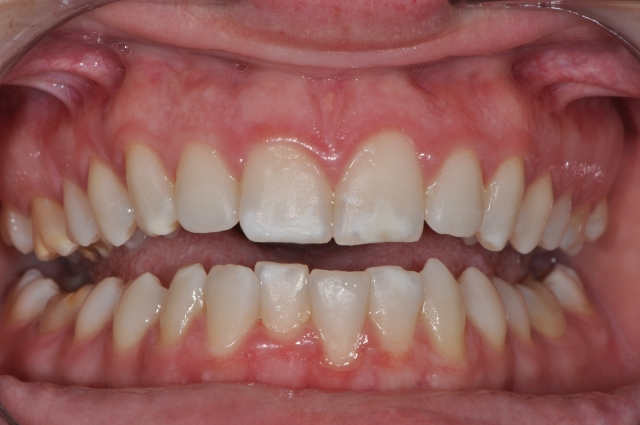

With the advent of MI Paste Plus, it’s possible to treat these areas before bleaching, significantly improving a patient’s smile. Applying MI Paste Plus to the tooth can remineralize the tooth surface, making whitening more successful and resulting in a more symmetric and esthetic tooth appearance.

- The patient should return in one month to document their progress. If white spots remain, a second in-office treatment with microetching, followed by phosphoric acid, can be repeated.

- Once the desired result is achieved, the patient can bleach their teeth if necessary and expect a more even and aesthetic result.